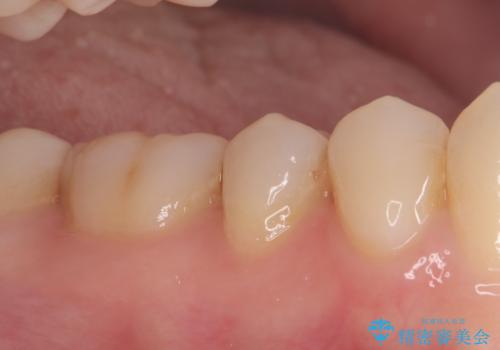

虫歯の部分のみを慎重に削除し、できる限り健康な歯質を残すように配慮しました。その後、強度があり適合性の高いセラミッククラウンを装着し、機能性と審美性の両方を確保。セラミックは変色しにくく、長期的な再発リスクも低減できるため、患者様にも安心していただけました。定期検診を継続することで、今後の虫歯リスクも管理していきます。